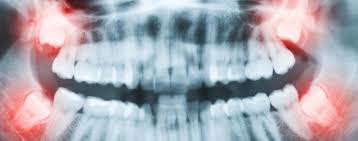

Bei einigen menschen brechen diese aber nicht durch das zahnfleisch hindurch, wodurch sie unter umständen schmerzen, schwellungen oder zahnfleischgeschwüre aulösen. Sich im kiefer befindende weisheitszähne Bei vielen menschen verursachen nicht durchgebrochene (retinierte) weisheitszähne keine beschwerden. Ein entzündeter weisheitszahn kann bei der entfernung, also während der op, weitere schmerzen verursachen. Darum müssen die fäden nach dem abheilen der wunden entfernt werden. Eine weisheitszahn op ist meist dann erforderlich, wenn diese nicht oder nur teilweise an die oberfläche gelangen und/oder wenn diese querliegen und so druck auf die nachbarzähne ausüben. Oben links jedoch sagte er, er müsste keine fäden ziehen da die wunde schon verheilt ist und keine fäden mehr zu sehen sind.alle wunden sehen im übrigen sehr gut aus! Weisheitszähne stehen zudem im verdacht, herzkrankheiten wie herzklappenfehler und rheumatische erkrankungen verursachen beziehungsweise verschlimmern zu können. Weisheitszähne brechen in der regel im alter zwischen 18 und 25 jahren als hinterste backenzähne durch. Wenn ein weisheitszahn durchbricht und im mundraum sichtbar wird, kann dies ganz schön schmerzhaft sein, besonders, wenn es sich um einen zahn im unterkiefer handelt. Die weisheitszähne (dens molaris tertius) zeigen sich in der regel erst nach dem 16. Wann ist eine weisheitszahn op notwendig. Aufgrund des komplett entwickelten gebisses finden die weisheitszähne innerhalb der zahnreihe keinen platz, um ungehindert durchzubrechen.

Aufgrund des komplett entwickelten gebisses finden die weisheitszähne innerhalb der zahnreihe keinen platz, um ungehindert durchzubrechen. Es hilft nicht, wenn man versucht, diese einfach zu ertragen, da dies sich eher negativ auf die heilung auswirkt und den körper schwächt. Dies kann zu zahnverschiebungen und beschädigung von nachbarwurzeln führen. Bereits durchgebrochene weisheitszähne sind die weisheitszähne schon voll durchgebrochen, lassen sich diese meist schnell und unkompliziert ambulant ziehen. Oft entdeckt der zahnarzt die weisheitszähne zufällig auf dem röntgenbild, solange der patient keine Denn solange die lokale betäubung wirkt, sollten sie auf mahlzeiten ganz verzichten. Sie können aber auch zu schmerzen, schwellungen, karies oder entzündungen am zahnfleisch führen. Lebensjahr, manchmal auch deutlich später. Weisheitszähne führen oft zu platzproblemen Wie lange eine wunde benötigt, bis sie verheilt ist, hängt aber auch maßgeblich davon ab, wie sich der patient nach einer weisheitszahn op verhält. Sehr harte sachen wie z.b. Nach etwa einer woche, in einigen fällen auch erst nach 10 oder mehr tagen, können die fäden gezogen werden. Bei vielen menschen verursachen nicht durchgebrochene (retinierte) weisheitszähne keine beschwerden.